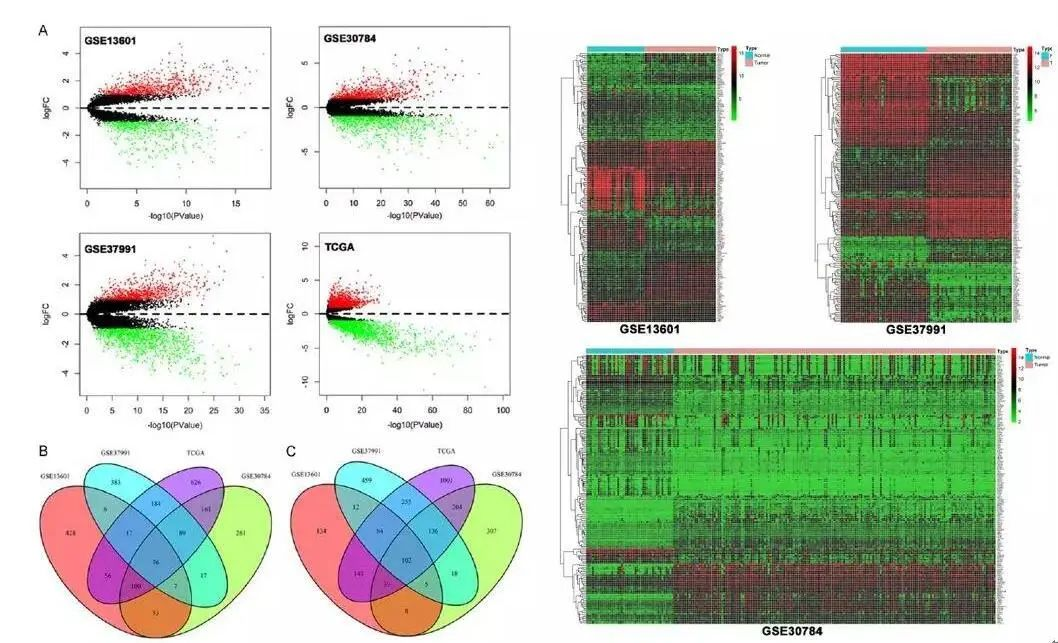

滑动查看更多 点击查看大图

期刊封面图设计

滑动查看更多 点击查看大图

论文图表排版

滑动查看更多 点击查看大图

论文图表美化

滑动查看更多 点击查看大图

数据分析与作图

滑动查看更多 点击查看大图

我们的数据分析人员全部来自清华、北大、中科院、协和、NIBS等国内顶尖研究机构,均发表过高分SCI论文,非常擅长生物、医学等领域各类型数据的分析与作图,可以完成基因组学、转录组学、蛋白质组学、代谢组学、表型组学、多组学、GEO和TCGA等数据库挖掘、临床病例数据分析、Meta分析、分子模拟与对接等各种数据分析与作图的项目。他们优秀的学术背景,保证了他们一流的分析水准。